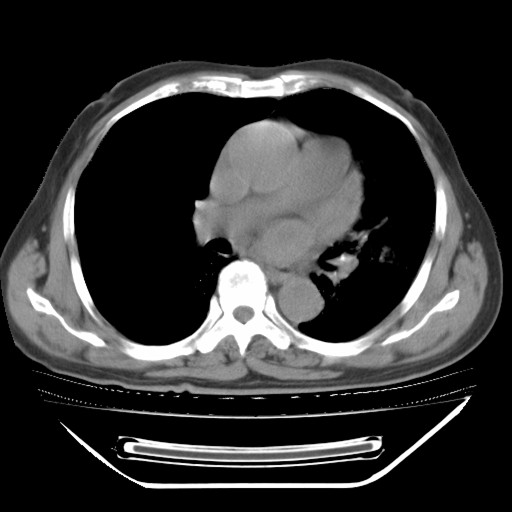

以下是引用hhcckk在2009-5-29 10:34:00的发言:[br]左下肺片絮状边缘模糊影,考虑感染,建议治疗后复查[br]